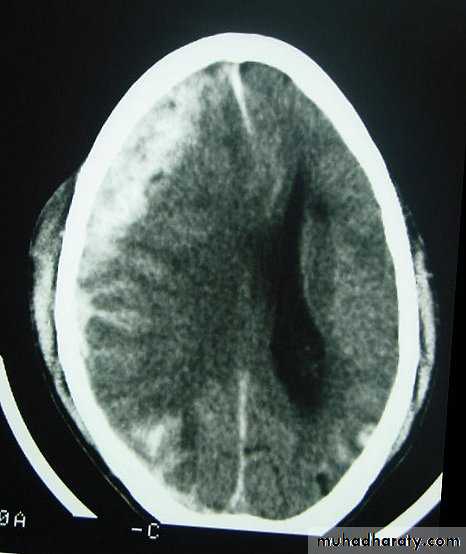

c. Intracerebral Haematoma

This is the least common of traumatic haematoma.They are due to areas of traumatic contusion coalescing into a contusional haematoma.

Disrupted cerebral tissue release thromboplastins that potentiate haemorrhage.

CT scan: appear as hyperdence lesions with associated mass effect and midline shift.Large intracerebral haematomas should be evacuated unless the patient’s neurological state is improving.

Small inracerebral haematomas may not require removal, but be aware that they can expand.